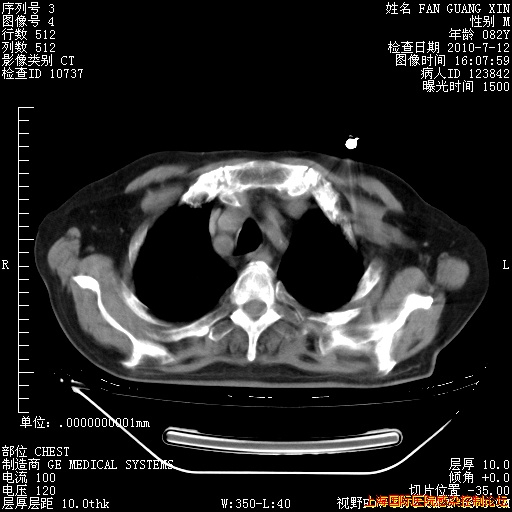

今天复查CT

今天CT

整整相隔30天的肺部CT好像有所好转啊。甲强龙减量第3天,需要观察体温。

海管,自昨日你和我通完话后,不知您岳父消化道症状有无缓解?体温怎样?阅读7.12日胸部ct,个人认为目前激素治疗是有效的,甲强龙减量是适宜的。因在抗痨治疗,需密切观察肝功、肾功能和血常规。不过,老年、长期住院和大量使用激素,很担心菌群失调发生